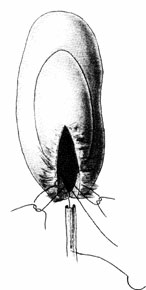

4. Ureterokalikoanastomoz. Variant vegyületet húgyvezeték alsó csésze (medencén intrarenalis

A 9. áramkör működése ureterokalikoanastomoz